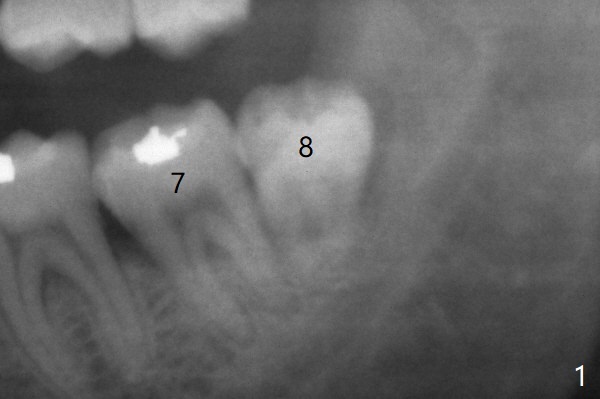

十三年后第二磨牙松动(图三),

磨牙间无骨     Last     Next